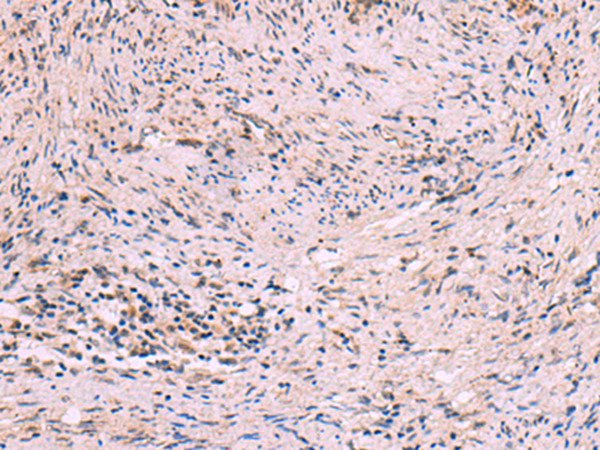

IHC positive control: |

Human cervical cancer |

IHC Recommend dilution: |

10-50 |